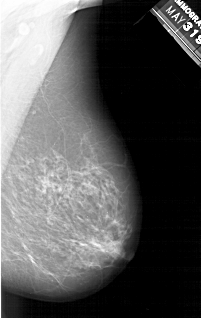

A_1214_1.RIGHT_MLO

RIGHT_CC LINES 5341 PIXELS_PER_LINE 3121 BITS_PER_PIXEL 12 RESOLUTION 43.5 NON_OVERLAY

RIGHT_MLO LINES 6031 PIXELS_PER_LINE 3811 BITS_PER_PIXEL 12 RESOLUTION 43.5 NON_OVERLAY